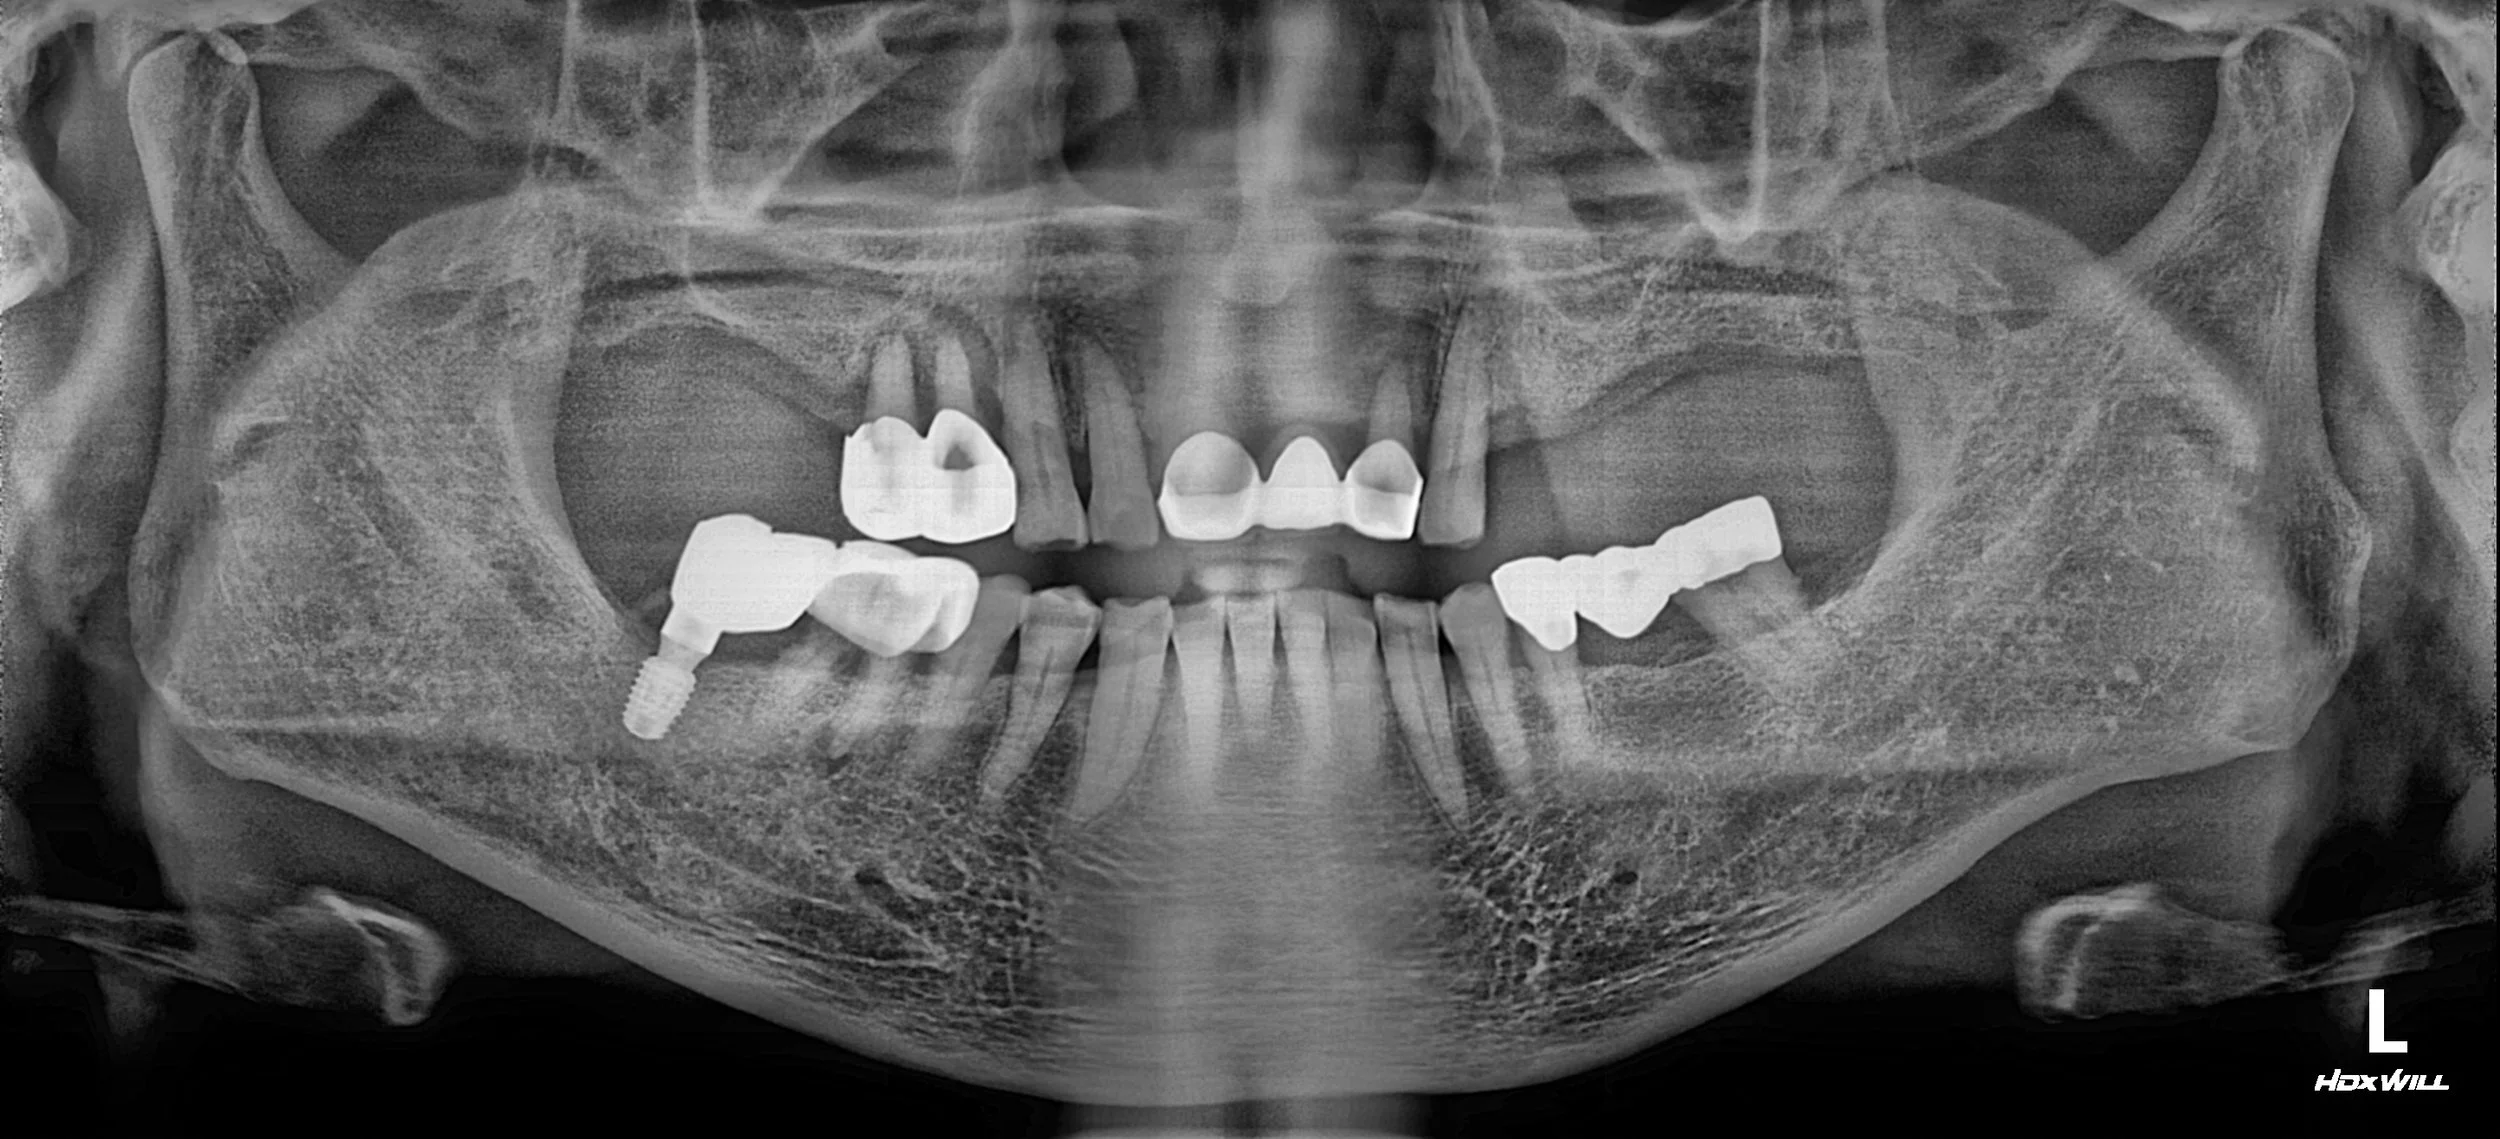

INTRA ORAL - AFTER

2. VDO Elevation & Implant Surgery: Dental implants were placed in the posterior edentulous areas. Simultaneously, the VDO was elevated using long-term provisional restorations. This "trial occlusion" allowed the patient to adapt to the new bite height and monitored for any TMJ discomfort.

3. Occlusal Stabilization Period: We maintained the patient in a stabilized temporary state for several months. This period ensured that the new posterior support was robust and the mandibular position was consistent before touching the aesthetic zone.

4. Final Aesthetic Restoration: Once occlusal stability was confirmed, the anterior teeth were restored. By resetting the occlusion, we were able to eliminate the flaring forces, providing a natural and stable anterior relationship.

The patient, who initially approached treatment with extreme skepticism, is now functioning with full confidence and expresses high satisfaction with both the comfort of his bite and the rejuvenation of his smile.